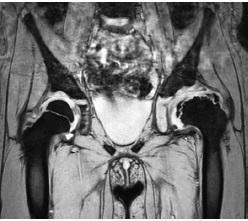

The MRI performed showed a significant improvement in the shape of the cartilage model and the absence of a necrosis focus in the femoral head, as well as an approximate physiological position of the labrum acetabulum (Fig. 6).

Fig. 6. Magnetic resonance imaging of cartilaginous models of the femoral head and acetabulum 6 months after surgery (explanations in the text)